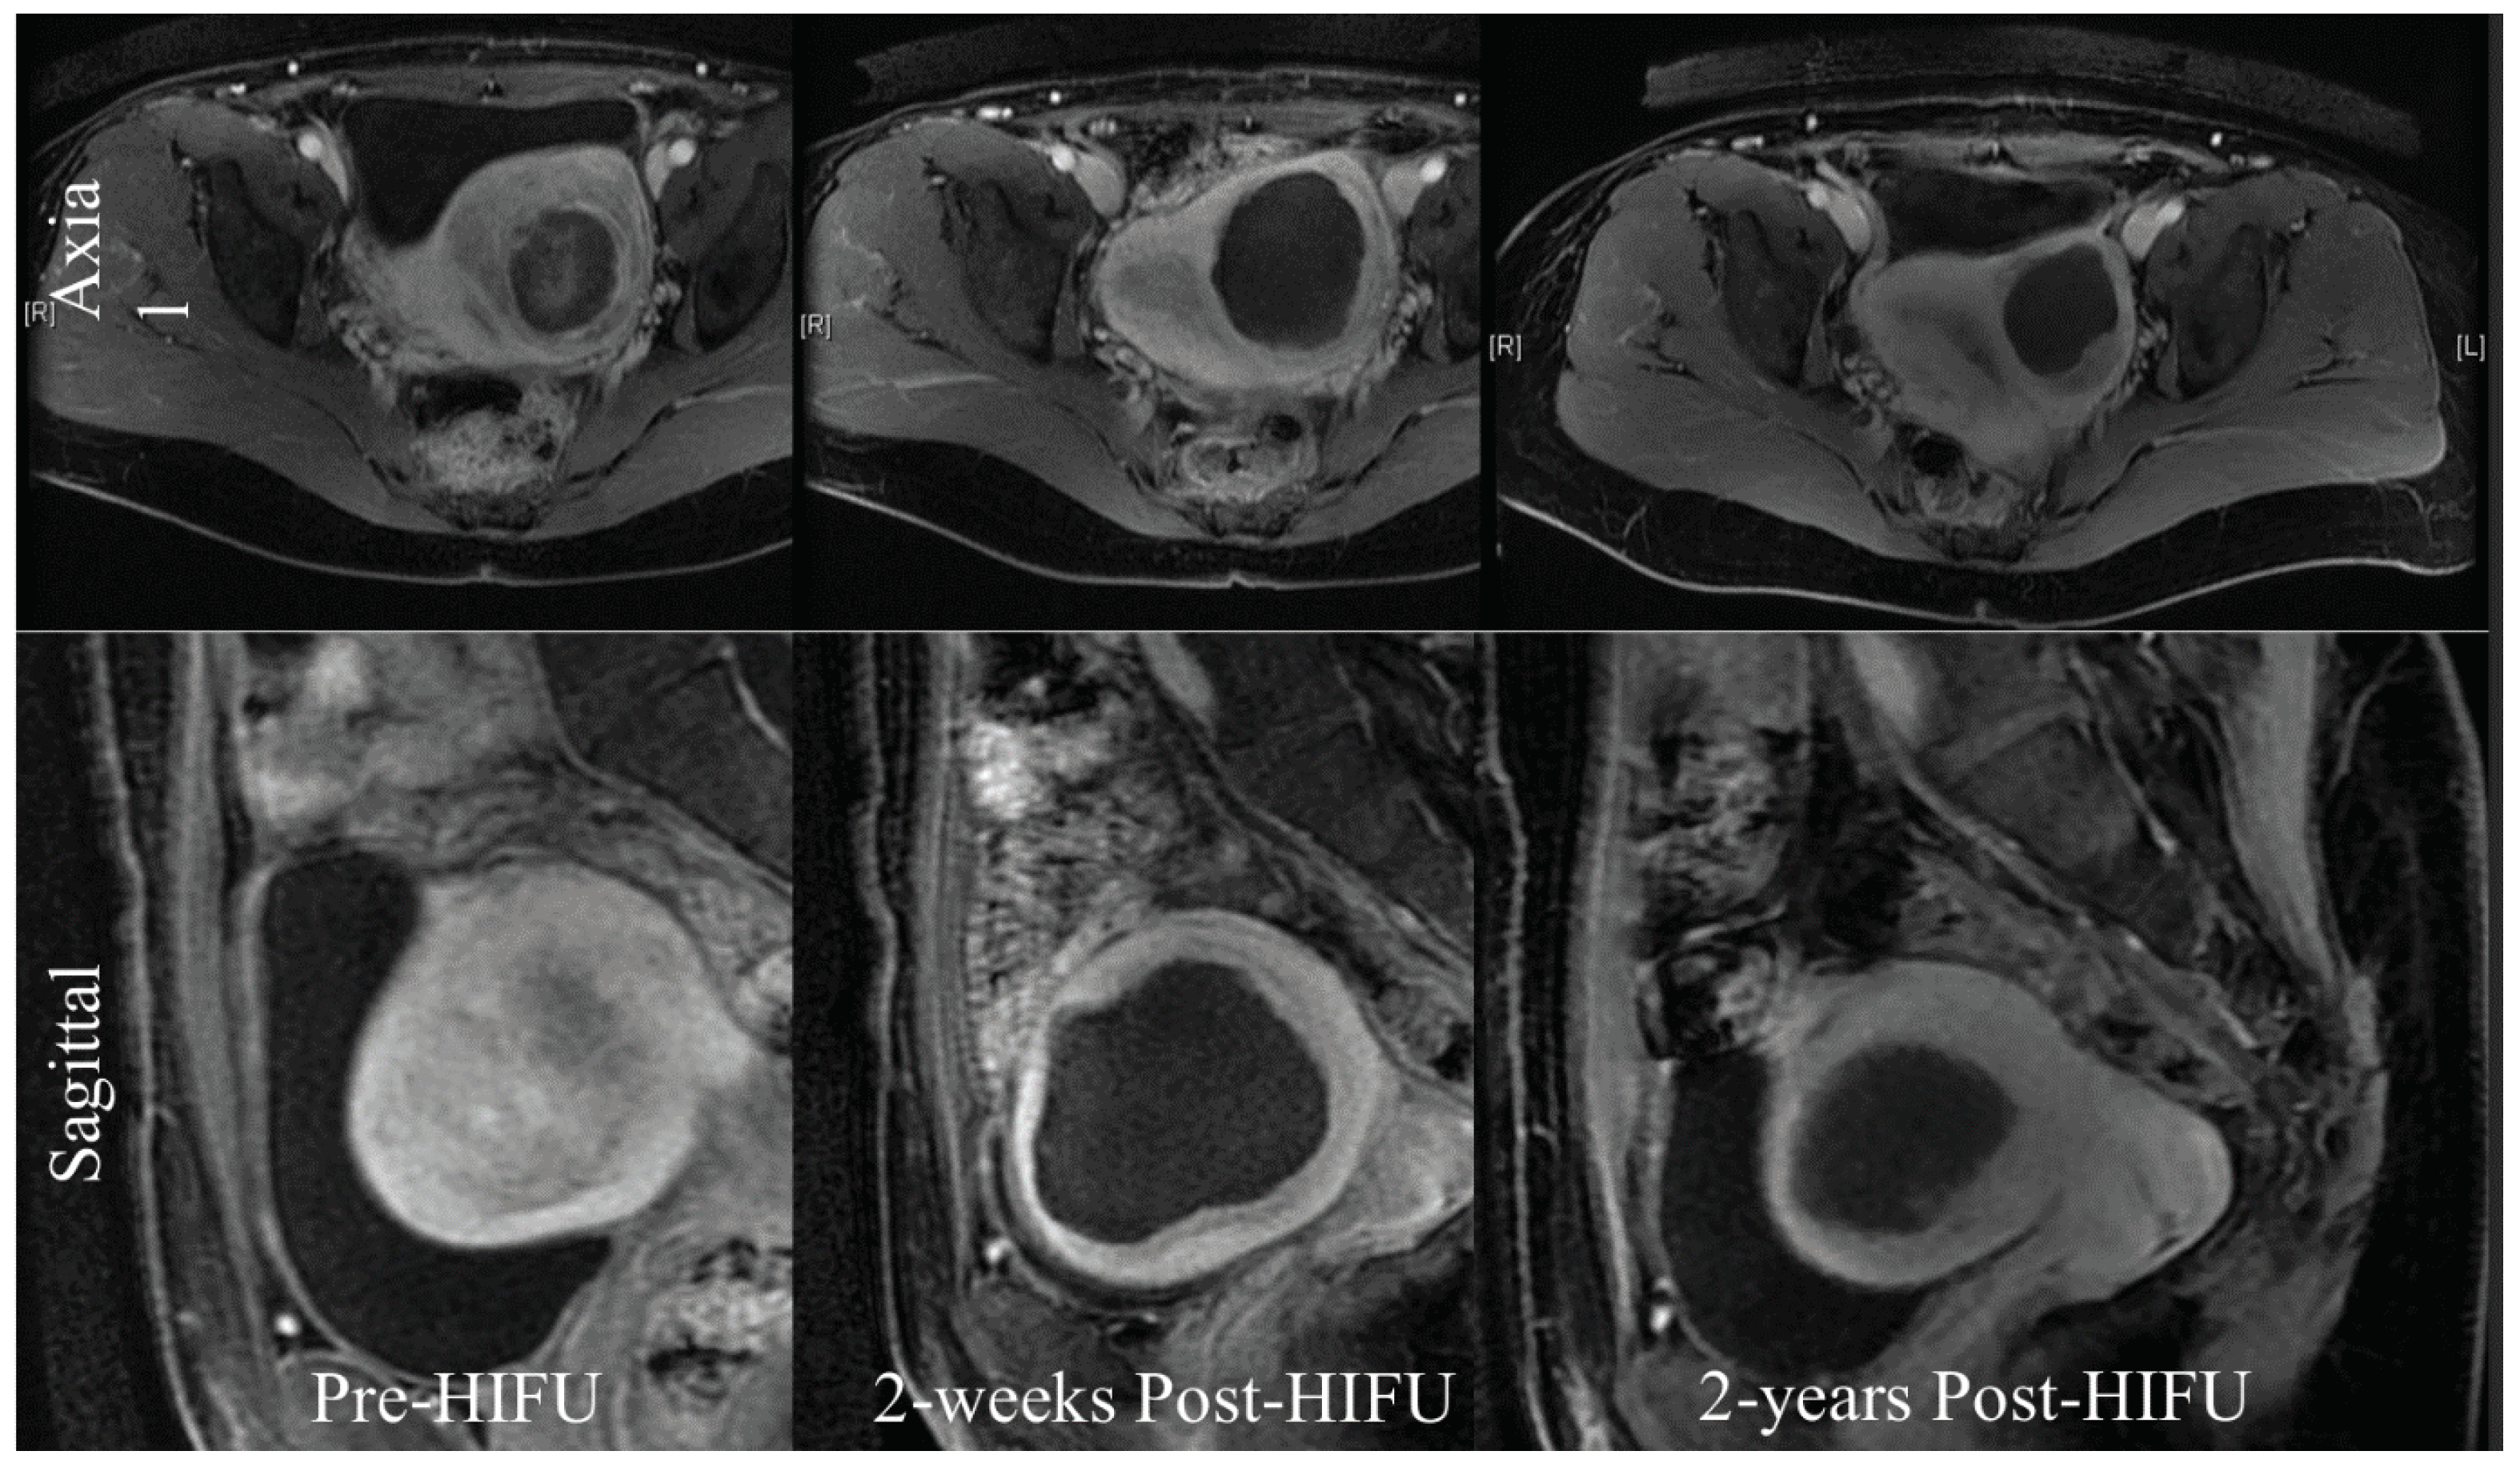

Figure 3. The treatment of uterine fibroids with HIFU (MRI).

In females, HIFU can be used to treat uterine fibroids, which occur between 20% and 25% of women of childbearing age [37]. A study from 20 centres in China in collaboration with the University of Oxford under the IDEAL framework [24] of a prospective collaborative cohort study looked at 2411 Chinese women with symptomatic fibroids and compared the outcomes from (HIFU) and surgery. 1353 women received HIFU, 472 hysterectomy and 586 myomectomies. Quality of life improved more rapidly after HIFU than after surgery, with fewer side effects and a shorted hospital stay longer-term quality of life outcomes were similar.

Oxford University Hospitals conducted the first study of HIFU treatment for this condition on an NHS population [38], [M1] treating a total of 14 fibroids. These patients were then monitored for a two-year period. No serious adverse events were recorded, but one patient with a surgical scar from a previous caesarean section had a secondary degree skin burn. Significant improvements were noted in mean symptom severity scores. In summary this study suggested that HIFU ablation led to a substantial improvement in symptoms over a 2-year time period. The occurrence of adverse events was low, with the exception of the skin burn which led to a change in protocol with no further patients being treated though a previous scar.